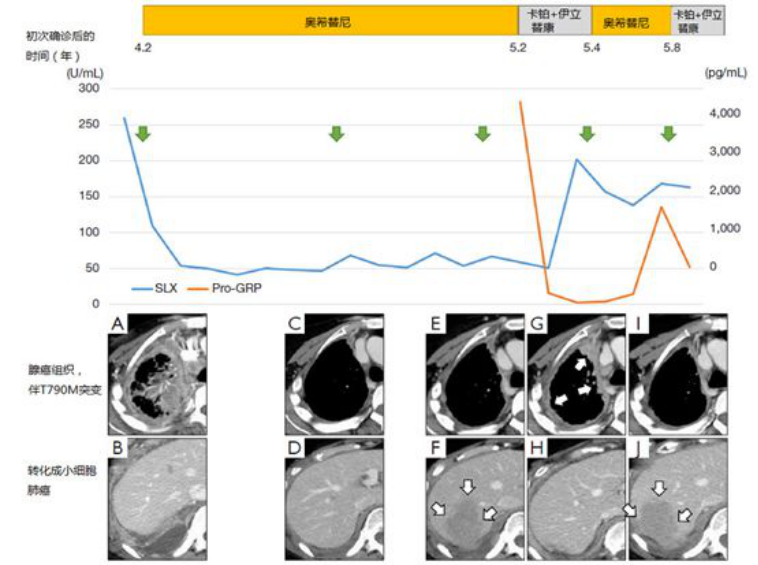

这里列举一例奥希替尼轮换治疗。一女性患者,61岁,晚期肺腺癌伴脑转,L858R阳性,先后使用吉非替尼、厄洛替尼、化疗,阿法替尼治疗了4.2年。患者的右胸膜转移灶测得T790M突变(组织为腺癌),但发现右横膈膜附近的胸膜肿瘤转化成小细胞肺癌。患者使用奥希替尼及化疗(卡铂 伊立替康)轮换治疗,在一处病灶发生进展后立即切换另一方案,具体见下图。